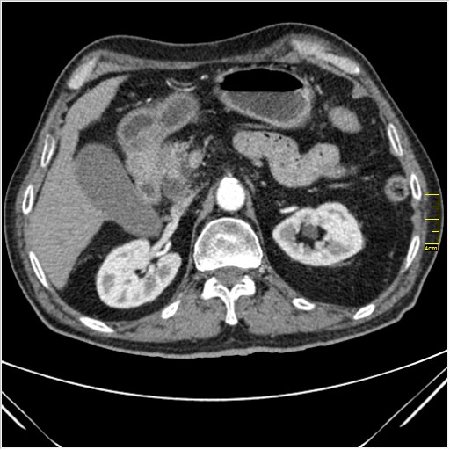

Мужчина 62 года с желтухой

Опухоль головки поджелудочной железы, расширение холедоха и панкреат. протока (Double Channel sign)

Карциномы панкреас гиподенсны на КТ с болюсом, т.к. содержать много соединительной и фиброзной ткани, в отличие от нормальной ткани железы, которая (как любая железа) хорошо васкуляризирована. Поэтому если видим в панкреас солидное гиподенсное образование - всегда настораживает на предмет рака. Второй момент: обязательная оценка взаимоотношения опухоли к ВБА и ВБВ, на предмет оценки операбельности.